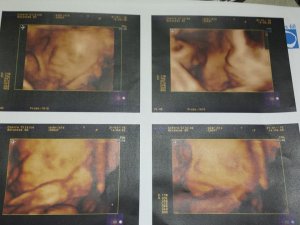

Tomás está fenomenal, ya pesa casi 1,900 kg y me he hecho la última eco 5d del paquete que teníamos. Lo hemos visto sonreír y sacar varias veces la lengua, aunque ya a esta altura el bebé está tan grande que suele pegarse a la placenta y no se puede ver tan nítido.